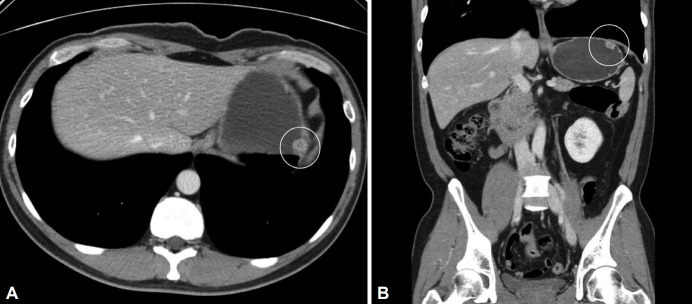

A Subepithelial Lesion of the Stomach Observed During Screening Endoscopy.

胃镜检查时发现胃上皮下病变。